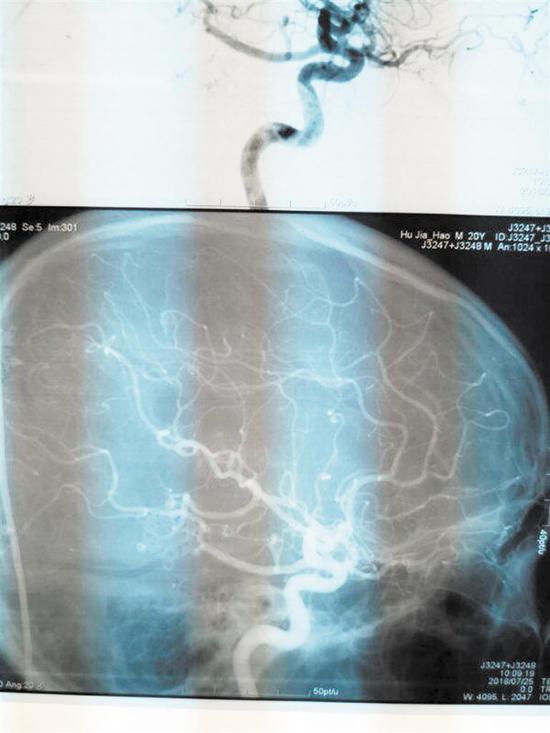

術后CT圖術后CT圖

為了隨時觀察小陳的情況,陳淳一直在NICU守護著。“此手術為神經外科4級手術,致殘率、死亡率高。手術后我們一直擔心會有如癱瘓、失明等后遺癥出現,幸運的是,小陳第二天就蘇醒了,神志清醒,無后遺癥出現。復查DSA,他的畸形血管團全切,恢復情況良好。”陳淳說。

陳淳提醒:精神持續緊張、血壓突然升高等都會成為先天性腦血管畸形誘發病因,在沒有外因的情況下,如果經常出現劇烈頭痛或劇烈嘔吐等情況應排查一下頭部是否存在血管畸形,如CT頭部磁共振或腦血管造影等是診斷腦血管畸形的最可靠和主要的診斷方法。